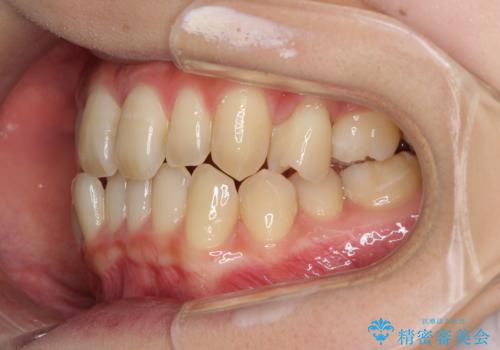

奥歯の反対咬合 上顎骨を拡大してインビザラインで矯正

- 奥歯の反対咬合を気にして来院された患者様です。

反対咬合は上顎骨の幅が下顎骨よりも小さいことが原因なので、拡大装置により骨幅を広げて上下関係を改善し、その後インビザラインにて歯並びを整えることとしました。

反対咬合が改善され、食いしばり癖もなくなり、顎関節の負担が軽減されました。